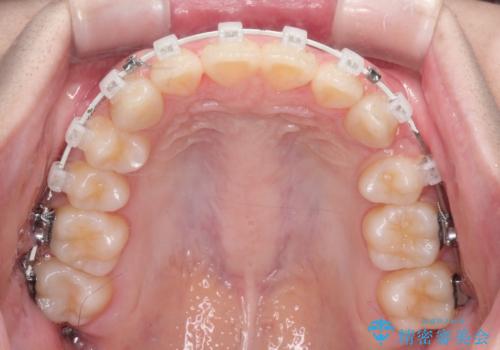

【ワイヤー矯正】前歯の真ん中を合わせたい。

- 前歯が出ている事を主訴に来院されました。

上と下の前歯がずれているため、抜歯を行い前歯の真ん中を合わせる治療計画を立ててワイヤー矯正にて治療を行いました。

途中、矯正用のアンカースクリューを使うことで、最終的にきれいに前歯の真ん中を合わせることができました。